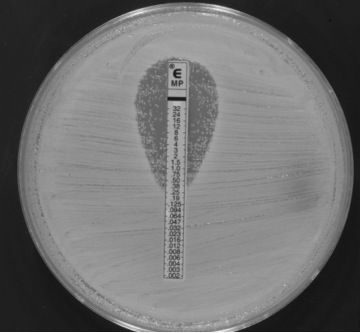

This is a not so infrequent meropenem E-test of a carbapenemase-producing K. pneumoniae (OXA-48). There is a well-defined halo around the stripe but as it can be easily seen, there are colonies within the halo.

- What do these inside-the-halo colonies mean?

- Are these colonies resistant to meropenem?

- Mutant, heteroresistant strains or simply an artifact?

- How should MIC be read?